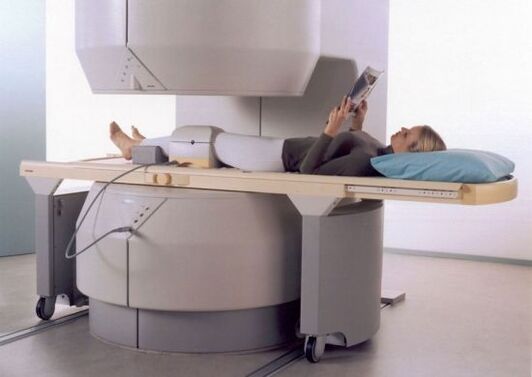

Եթե ռենտգենն այնքան էլ տեղեկատվական չէ, բժիշկներն առաջարկում են ՄՌՏ անցնել, որտեղ կարող եք բժշկին հետաքրքրող տարածքը մի քանի կանխատեսումներով հետազոտել:

- մագնիսական ռեզոնանսային պատկերացում;